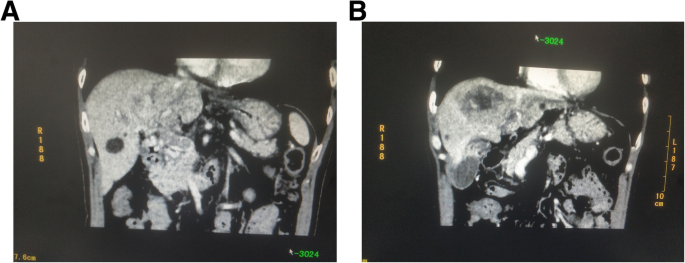

Laboratory blood tests (Table 1) were administrated and revealed a high level of the AFP tumor marker (337.83 μg/L). There were no signs of Hepatitis virus infection. The patient was found to have Child-Pugh Class A liver function, and abdominal computed tomography with enhancement and vascular reconstruction revealed that there was a lesion in section IV of the liver, with an approximate diameter of 5 cm. In addition, the tumor demonstrated enhancement in the arterial phase and no enhancement in the portal and delayed phases. There was a portal vein filling defect involving the main portal vein trunk, left portal vein, and right portal vein (Fig. 1). The patient was diagnosed with HCC with PVTT, which was accompanied by a grade VP4 portal vein invasion.

Representative computed tomography scan images before the operation. a. White circle showing the portal vein tumor thrombus, and that the portal vein main trunk was invaded; this was classified as grade VP4. b: White circle denoting the tumor located in the liver section IV; the approximate diameter is 5 cm. The tumor showed enhancement in the arterial phase and no enhancement in the portal and delayed phases